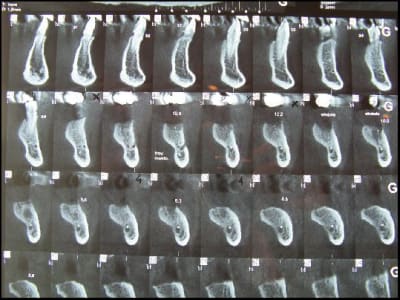

Pépé me demande de te fournir les documents ci joints , n'en abuse pas sauf si tu as prévu un voyage en Jamaïque .

;))))))